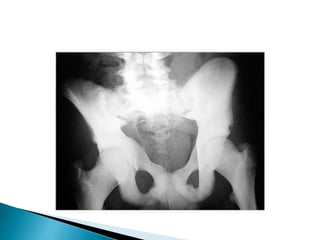

 Paget diseaseis a chronic disorder of unknown origin with increased breakdown of bone and formation of disorganized new bone. The most common appearance is the mixed lytic-sclerotic

.  In thiscase we see the pathognomonic triad of bone expansion,  cortical thickening and trabecular bone thickening in the mixed lytic and sclerotic phase of Paget's disease of right hemipelvis